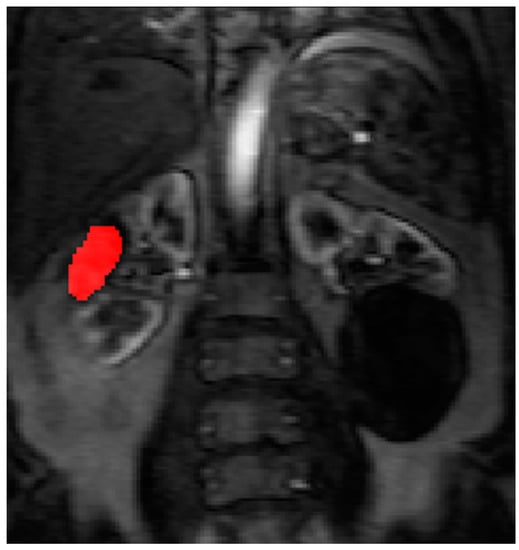

Contrast agent concentration-time curves were approximated using relative change in signal (compared to baseline) against time [13]. To assist in identifying the tumour and drawing the ROI, a map of maximum contrast agent concentration was generated. Using the map, ROIs were drawn to encompass the renal tumour pre RFA (Figure 3) and the whole zone of ablation post RFA (Figure 4).

The pre RFA renal tumour and post RFA zone of ablation in every patient were saved and anonymized within the same dataset. Pre RFA, the ROI outlined the bright area which represents the enhancing renal tumour. In this cohort, some of the tumours had a cystic or necrotic component, but only the solid components were included in the ROIs. Post RFA, the ROI outlined the whole zone of ablation which is typically larger than the tumour to allow for the ‘surgical’ margin, this is the dark area on images that represents ‘dead’ renal tumour. If there is any bright area within the zone of ablation, this typically suggests area of enhancement and indicates that there is a viable renal tumour and this would be included with the ROI. This process was repeated for every slice containing pre RFA tumour and the post RFA zone of ablation. The regions for each slice were combined giving a volume of interest that covered the perfused renal tumour in the DCE dataset. This was then analyzed to extract concentration-time curves for the renal tumour before treatment and zone of ablation after treatment (Figure 5). The maximum slope of the tumour curve and the peak value of the AIF were determined.

Figure 3. The right renal tumour is sited at the mid polar region of the kidney and there is a large renal cyst at the lower pole of the left kidney. The ROI is drawn on the maximum concentration map generated by Platform for Research in Medical Imaging (PMI) software before RFA treatment.